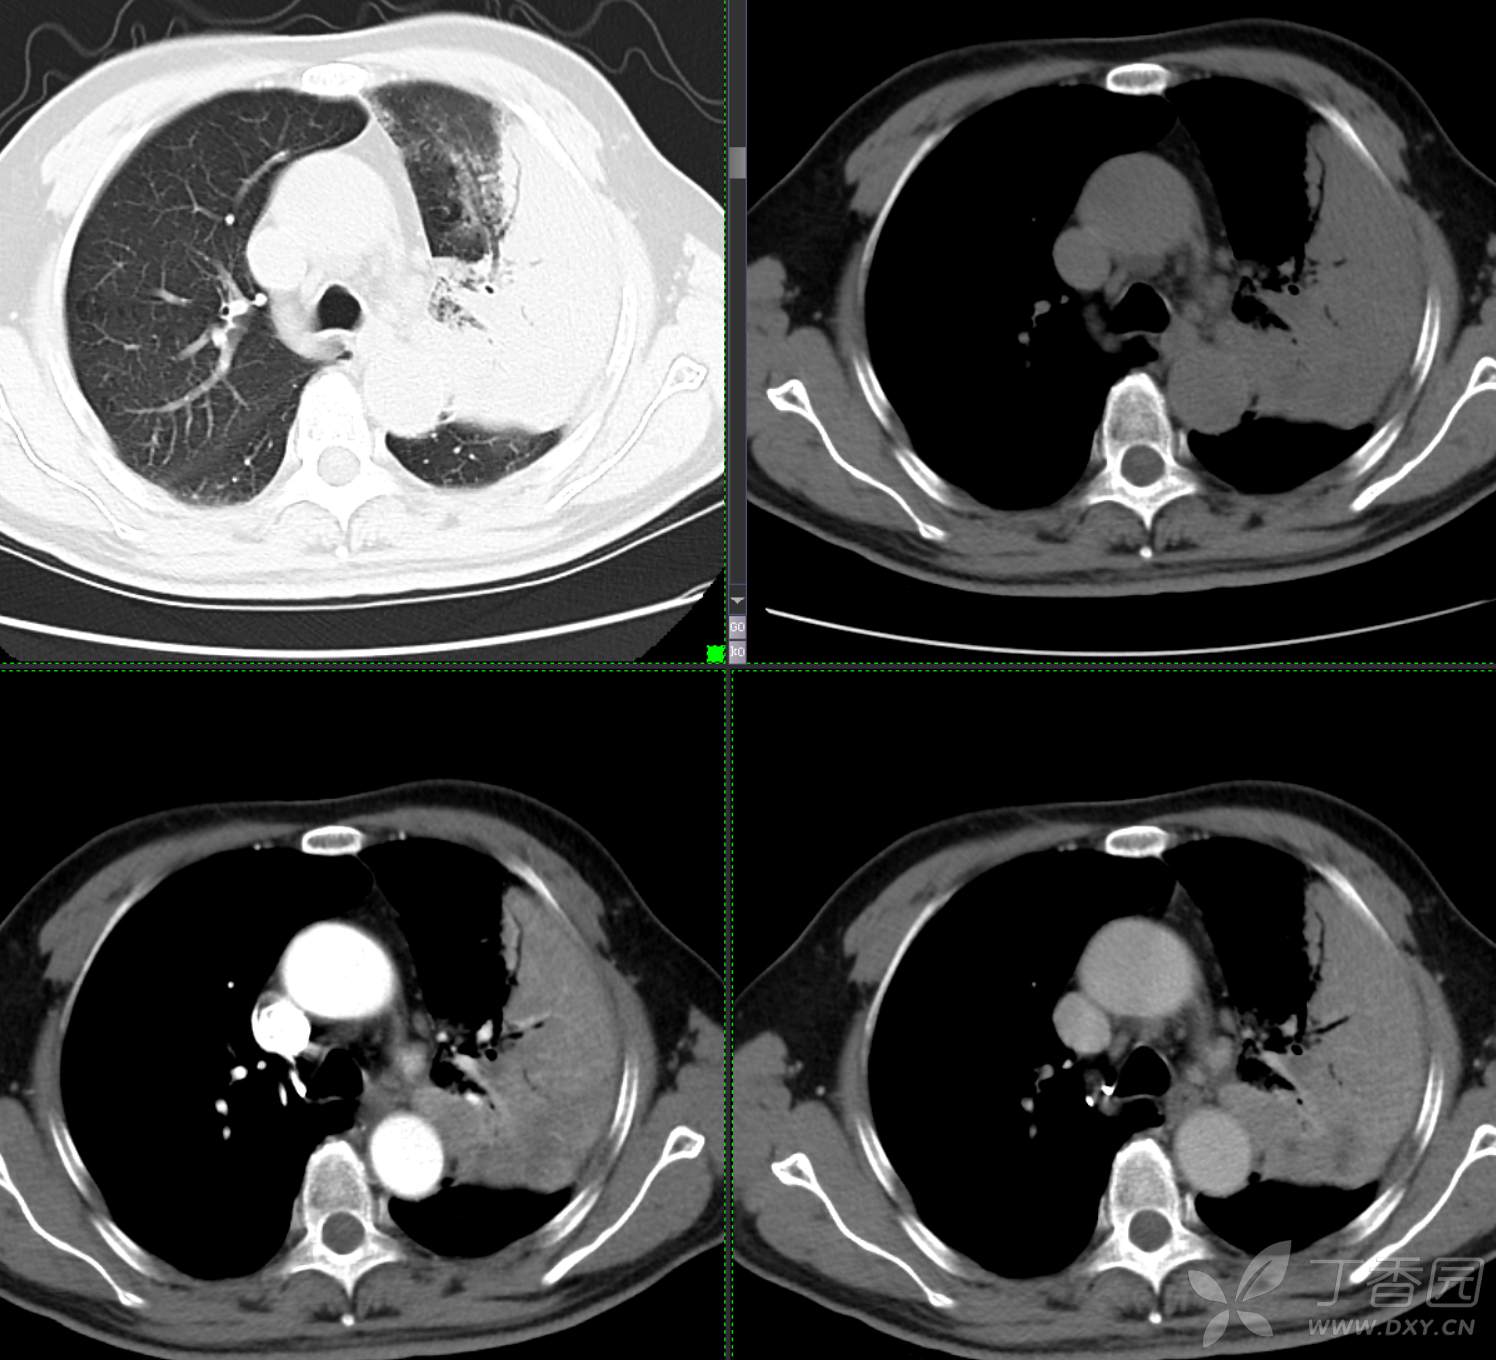

胸部29:大叶性病变,有征象,有特点,你的诊断?

患者性别:男

患者年龄:65

主诉:咳嗽2月余

简要病史:患者2月余前无明显诱因下出现咳嗽,干咳为主,夜间加重,伴咳痰,量中等,白粘痰为主,无明显胸闷气促,无恶心呕吐,无鼻后滴液,无发热畏寒,无鼻塞流涕不话,患者至当地医院就诊,考虑肺部感染,住院治疗,先后予“哌拉西林他挫巴坦针、莫西沙星针、美罗培南针、亚胺培南针、利奈唑胺片”抗感染治疗,患者咳嗽症状稍有好转,但仍存,为进一步诊治至我院门诊,现为进一步诊治,拟“肺部阴影、肺部感染”收治入院。